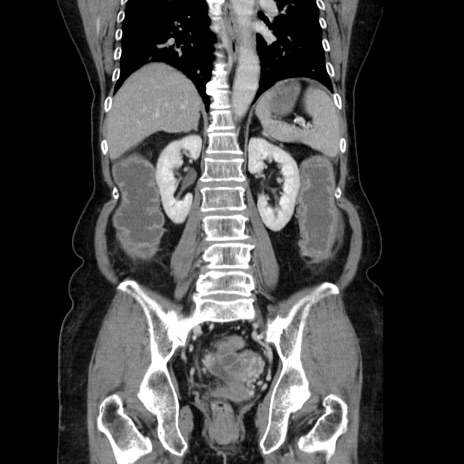

症例5(冠状断像)

【症例】70歳代女性

【主訴】お腹が張る

【現病歴】1週間くらい前から腹部膨満の自覚あり。昨日夜から増悪したため、本日救急外来受診。

【身体所見】意識清明、BT 36.5℃、BP 165/106mmHg、HR 80bpm、SpO2 98%、腹部:膨満、軟、自発痛・圧痛なし、触診にて不快感あり、腸蠕動音:減弱

【データ】WBC 12600、CRP 1.04